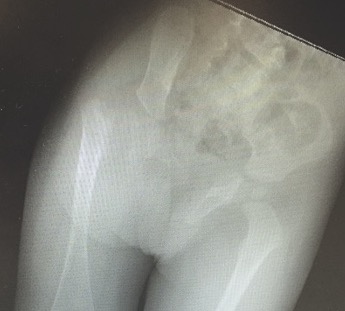

Class C

- no femoral head

- acetabulum severe dysplastic

- very short femoral shaft with bony tuft proximally

Class D

- femoral head & acetabulum completely absent

- femur consists of condyles only